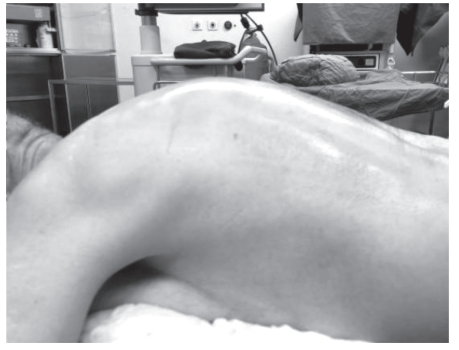

专科查体:脊柱后凸、左侧侧弯(见图1),右侧胸背部可见色素沉着,沿右侧 T6~T8 神经带状分布,伴痛觉过敏、痛觉超敏,无明显感觉减退,数字分级评分法 (NRS) 8 分。

图1 病人脊柱后凸畸形